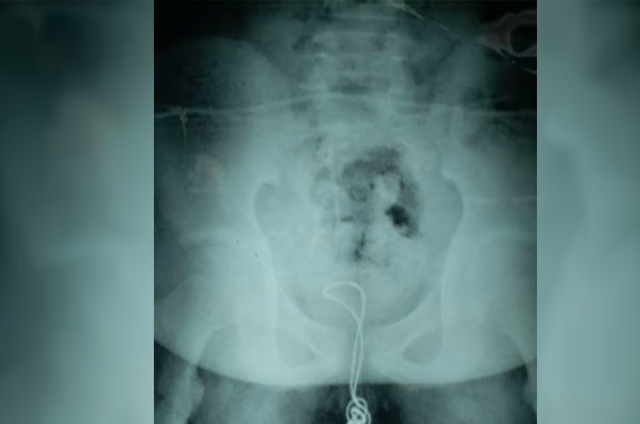

Xu Liyan, la uróloga residente del Hospital Infantil Harbin, dijo que el menor “cortó un extremo del cable y lo insertó en su uretra, el cable llegó a su vejiga, donde se enredó y terminó en un nudo, por lo que cuando trató de sacarlo, se quedó atascado”.

De acuerdo con Liyan, para retirar el cable fue necesario realizar un corte en la vejiga para encontrar el cable anudado. Tras cortar la parte enredada, extrajeron el cable restante a través de la uretra, de la misma forma en que entró.